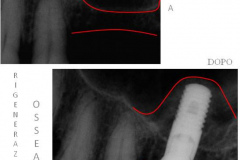

Nel corso degli anni si è assistito ad una vera e propria sviluppo ed evoluzione della chirurgia ricostruttiva (GBR: Guided Bone Regeneration) dei siti ossei atrofici, ovvero di quei siti che non presentano i requisiti minimi di volume per accogliere un impianto; di pari passo, abbiamo assistito ad un continuo sviluppo merceologico di superfici implantari sempre più performanti ed affidabili.